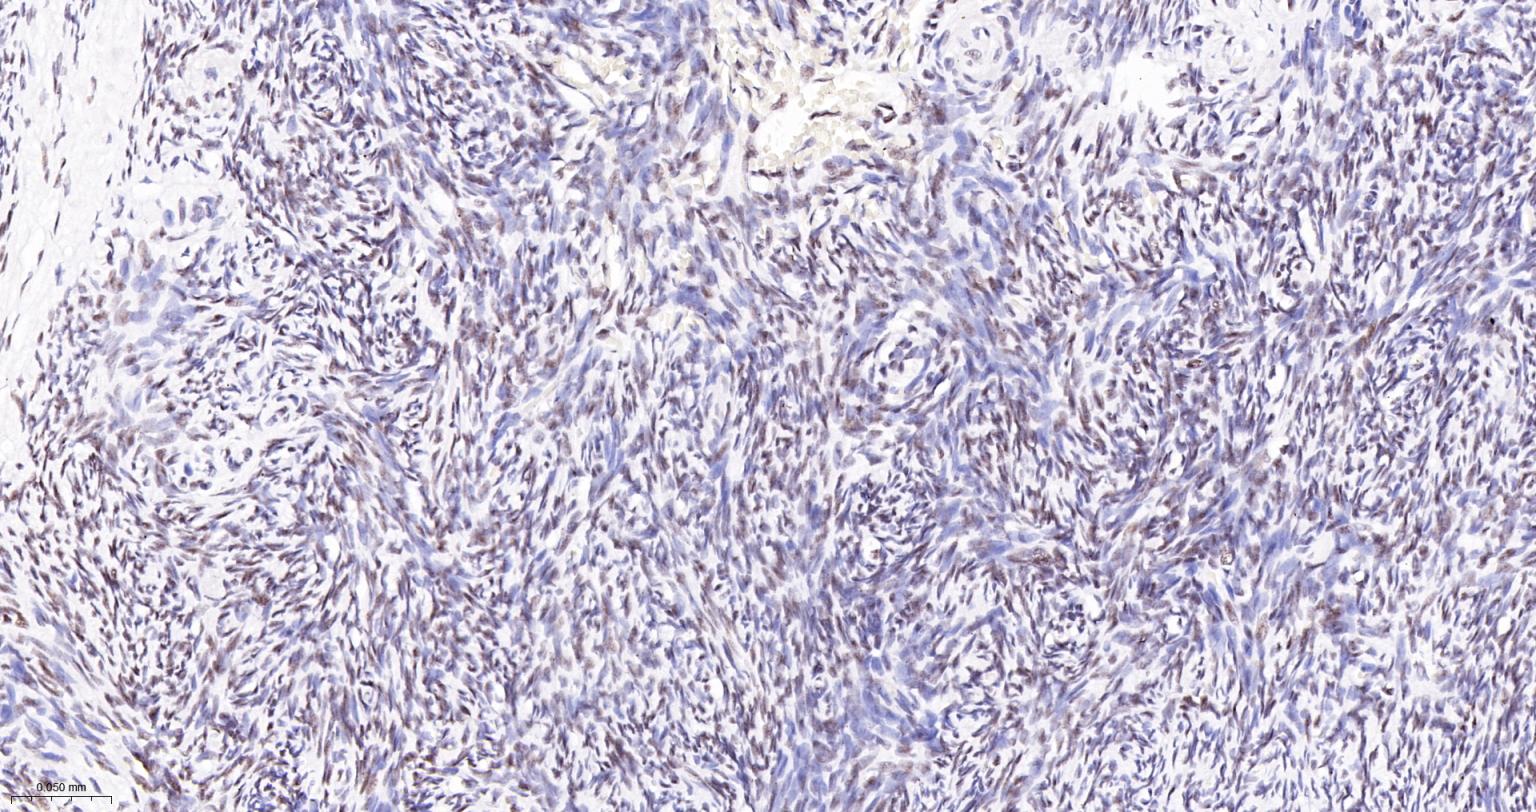

Paraformaldehyde-fixed, paraffin embedded Human Endometrial Cancer; Antigen retrieval by boiling in sodium citrate buffer (pH6.0) for 15 min; The section was incubated with USP39 Monoclonal Antibody, Unconjugated (bsm-63016R) at 1:200 overnight at 4°C, followed by conjugation to the bs-0295G-HRP and DAB (C-0010) staining.